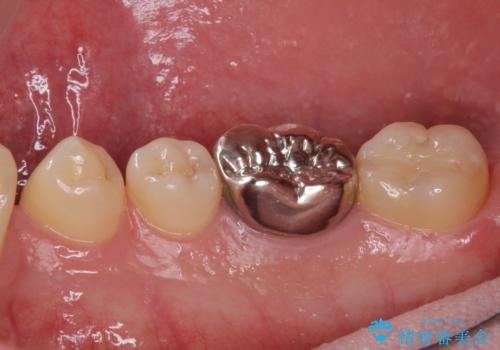

- 口を開けたときに目立ってしまう銀歯をセラミックに替えたいとのことで来院された患者様です。

以前むし歯治療を受けたときは時間がなかったため、近医で銀歯を入れたようですが、周囲の目線が気になるとのことでフルジルコニアクラウンにて補綴することとしました。